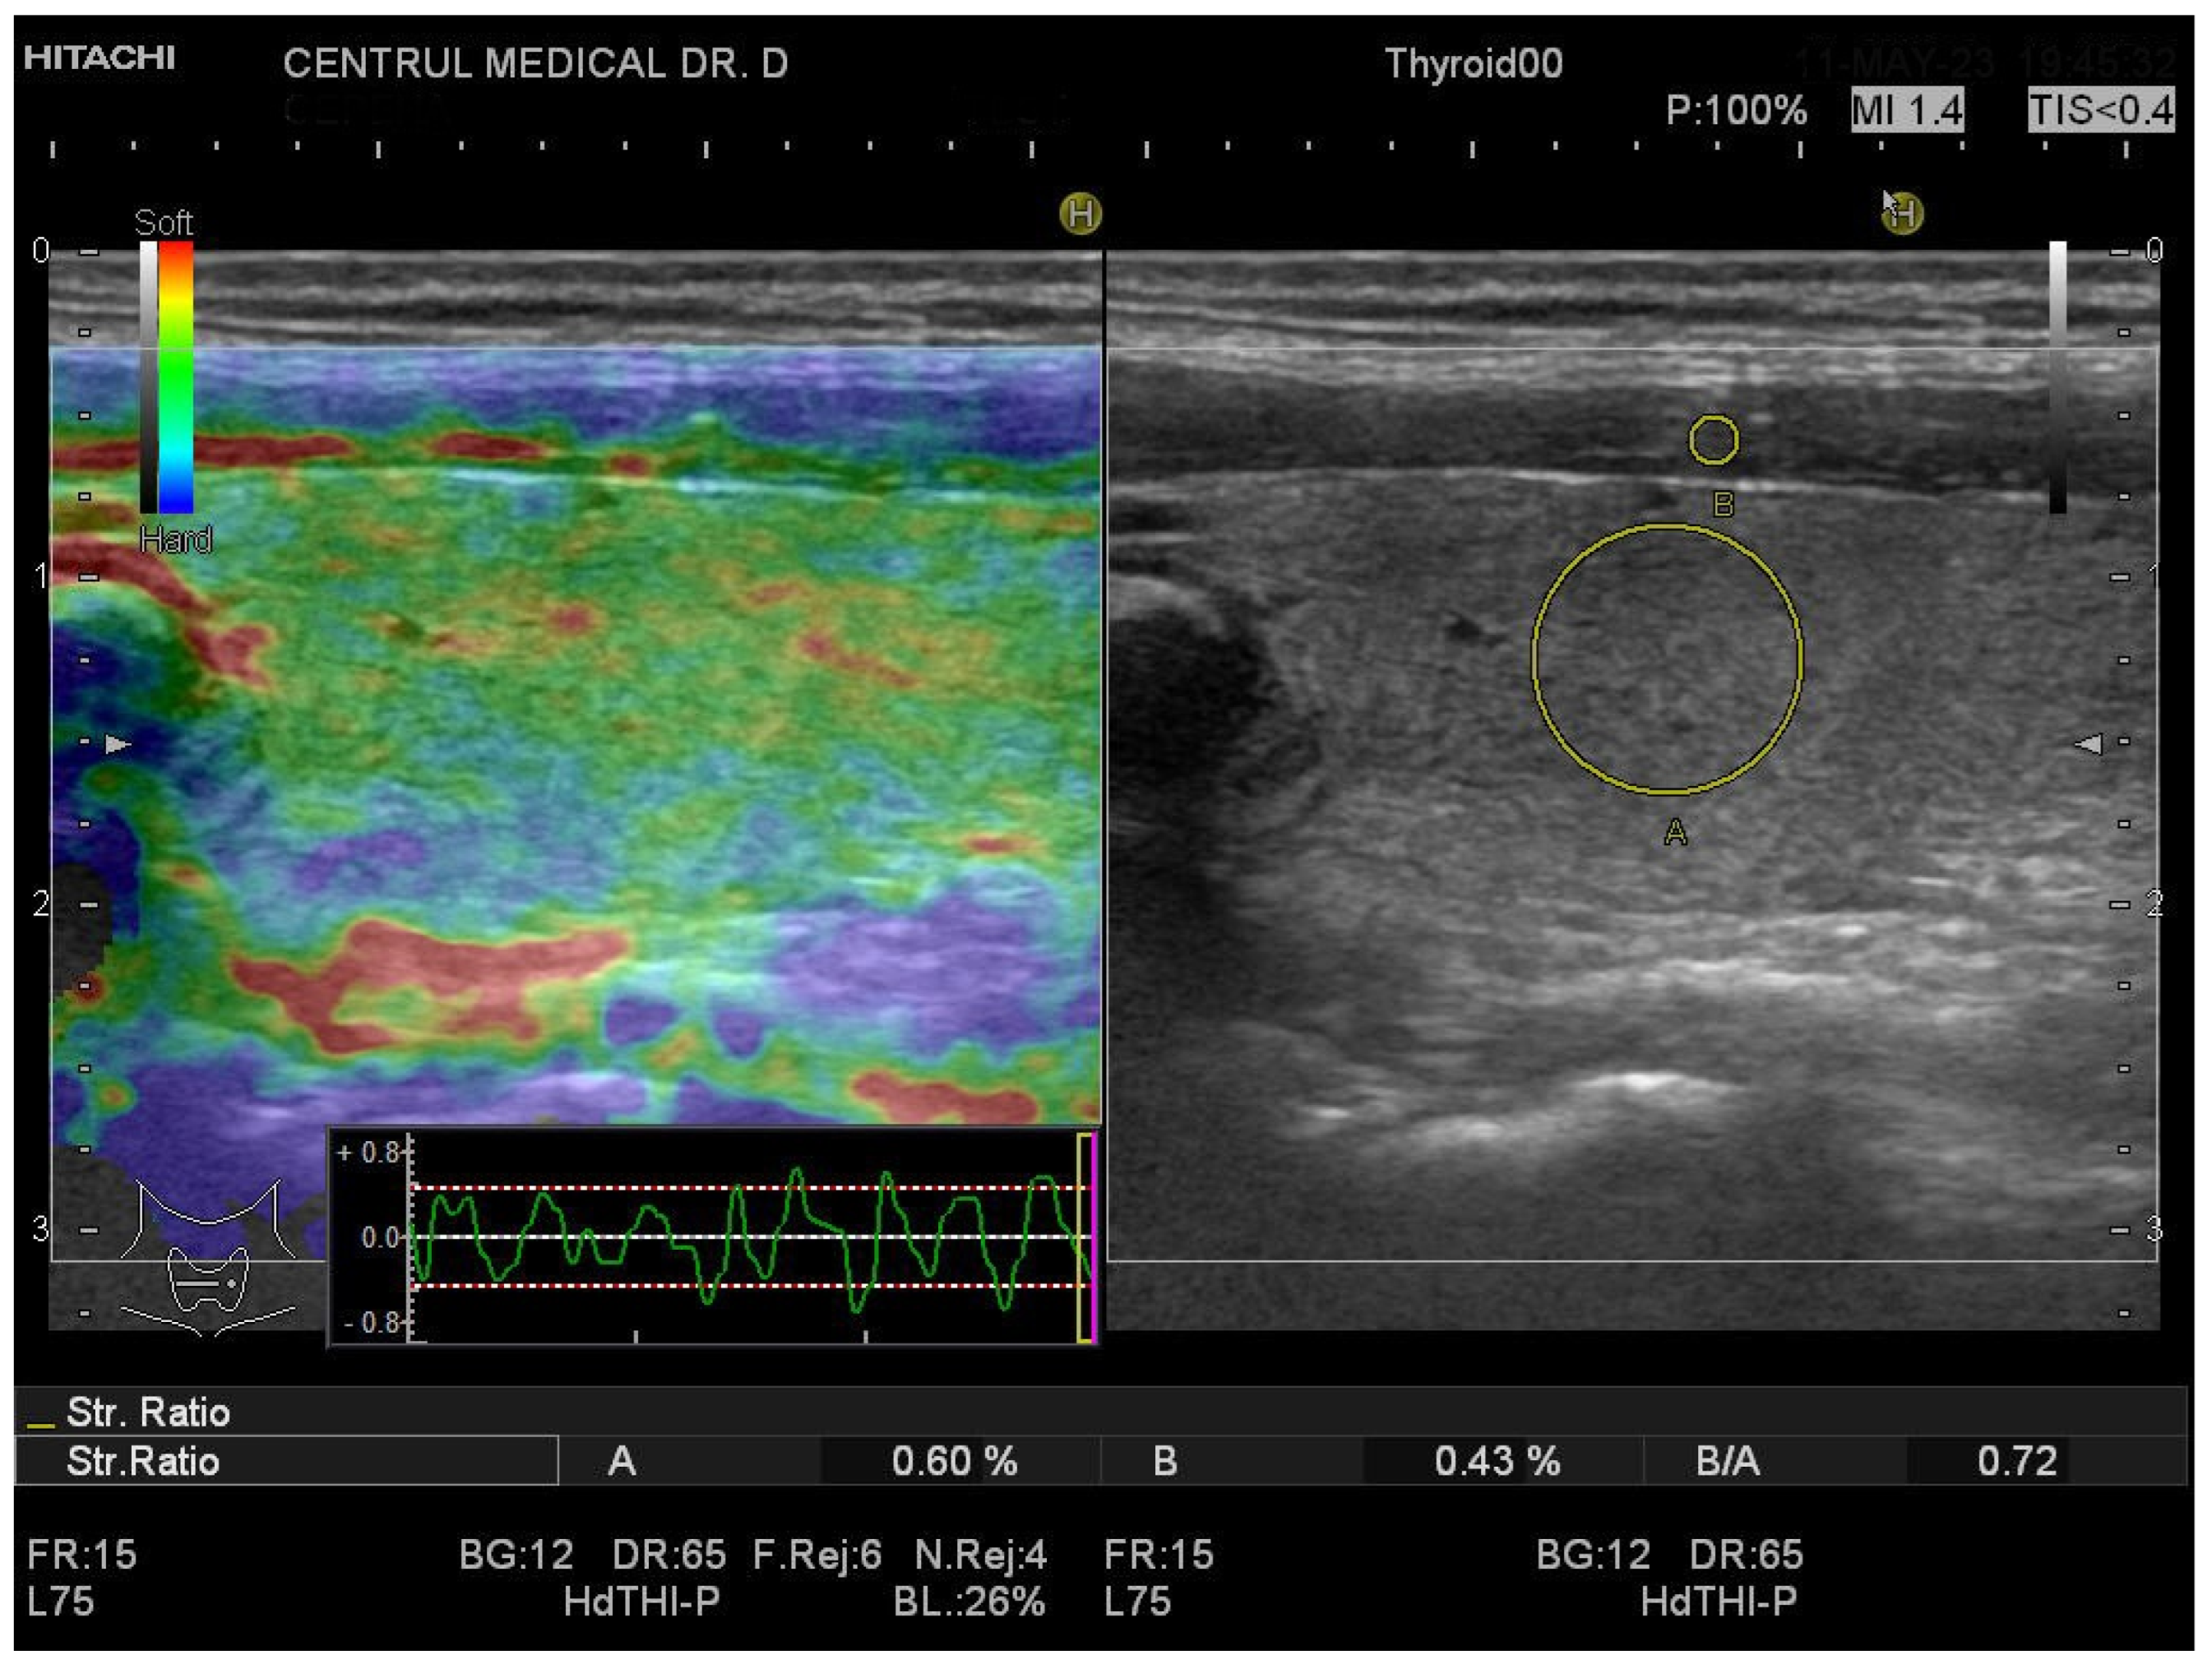

3.1. Strain Elastography Measurements

| SE | SR-THY | 1.2 (1.2–1.3) | 0.7 (0.6–0.9) | <0.0001 |

| SR-LL | 1.3 (1–1.5) | 0.7 (0.5–0.8) | <0.0001 | |

| SR-RL | 1.2 (1–1.4) | 0.7 (0.6–1) | <0.0001 | |